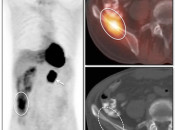

Respiratory motion is a particular imaging problem because the patient must breathe during the long acquisition time required for the PET imaging of the chest. If a normal full inspiratory breath-hold technique is utilized for the CT portion of the exam, marked misregistration will occur.

Breathing Techniques: To minimize lung misregistration, either shallow tidal breathing or a shallow end-expiratory breath hold during the CT exam is recommended.